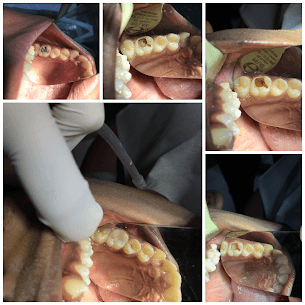

- TREATMENTS:

Direct Pulp Capping

- INFO:

Conservative treatment for 16-year-old with deep caries near pulp